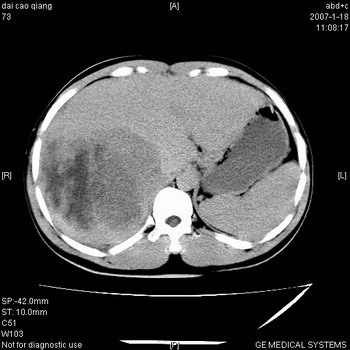

符合巨块型肝癌表现:

1、平扫低密度,增强后表现为快进快出。

2、动脉期可见迂曲的动脉供血血管

3、并可见门静脉右支癌栓形成

4、可见假包膜

5、腹主动脉旁结节影,考虑肿大淋巴结。

肝右叶巨块型肝癌,伴瘤栓形成,肿瘤有包膜,可见动静脉短路。

肝右叶巨大不均匀低密度肿块,前缘有假包膜,增强明显的呈快进快出表现,门脉右支有癌栓,病人虽然年轻但还是首先考虑肝右叶巨块形肝癌,病人血象高只能说有合并感染。不支持肝脓肿。